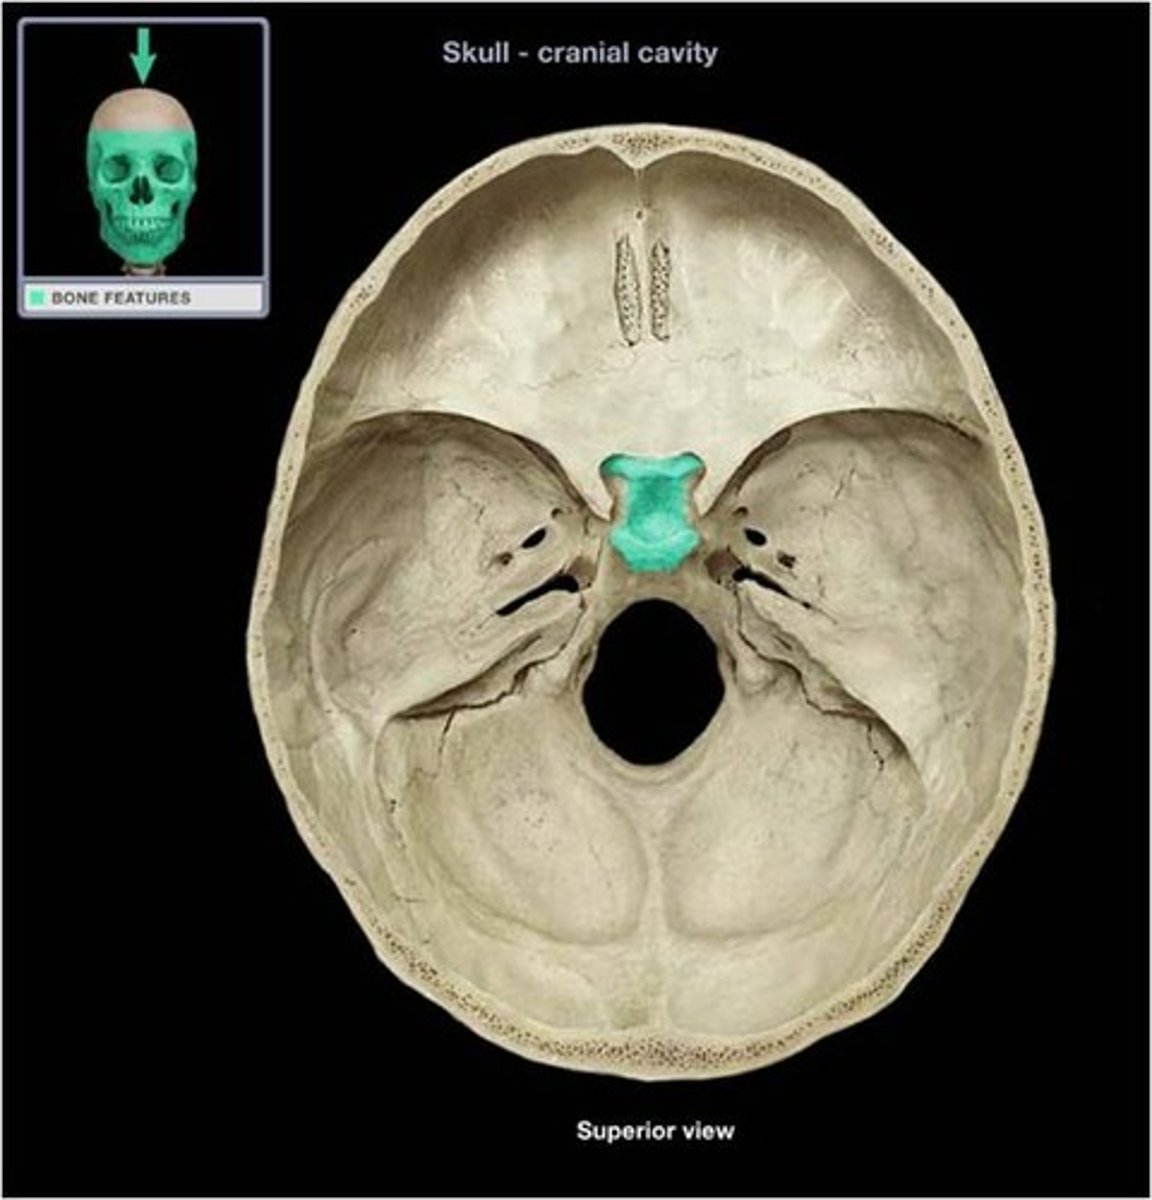

Sella Turcica

Depression in the sphenoid bone where the pituitary gland is located